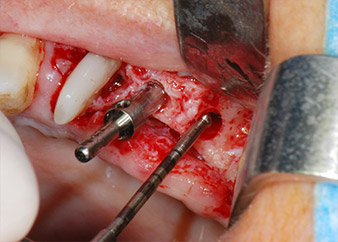

En el siguiente paso, los lechos del implante se prepararon en las posiciones 25 y 26 con instrumentos rotatorios, utilizando un contra-ángulo con un coeficiente de transmisión de 20:1 (WS-75 L, W&H), junto con el nuevo potente motor de implantes Implantmed de W&H (figuras 8 y 19).

La preparación final junto al seno se realizó de nuevo con un inserto piezoeléctrico (Piezomed S2).

Antes de la colocación del implante y tras la verificación de que la membrana de Schneider estaba intacta (figura 9), la base interna del seno se aumentó en las dos posiciones del implante con un material sustituto de hueso xenógeno (Bio-Oss, Geistlich Biomaterials) (figura 10).

A continuación, los implantes (Restore, Keystone Dental, 3,75 mm de diámetro, 8,0 mm de longitud) se colocaron con el motor de implantes (figuras 11 y 12).